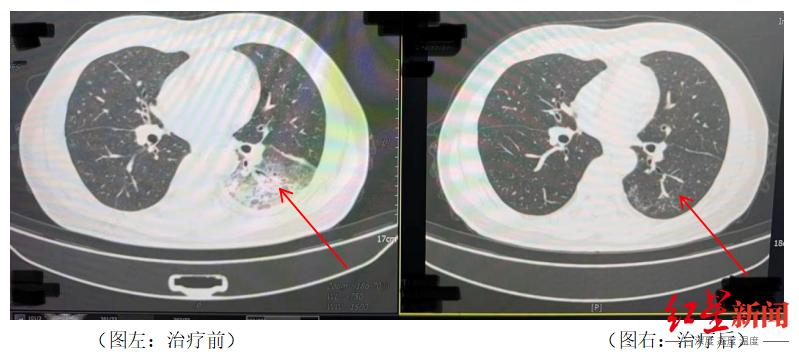

当他的家人看到这一幕时,他立即被送往医院。胸部CT显示,李先生的左肺已经出现了大面积的白色图像,几乎占了肺的一半。经检测,最终确认为嗜肺军团菌肺炎。

△治疗前和治疗后李先生肺部的对比。